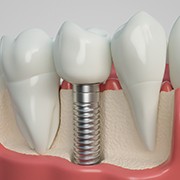

Rather than simply giving you a fake tooth that sits on top of your gums, dental implants are held firmly in place using a small titanium post that is surgically inserted into your jaw that will naturally bond with the surrounding bone. Not only does this give it the security of a natural tooth, but it also ensures the long-term health of your gums and jaw.

Osseointegration usually takes between three to six months. During this time, the bone around the implants will start to merge with the metal. Once osseointegration is complete, your implants can be considered part of your mouth, enjoying enhanced stability and durability as a result.

After successful osseointegration, we’ll schedule a second surgical procedure to place an abutment. This procedure will be much smaller than the initial implant surgery. All we need to do is place the metal connector pieces known as abutments to the top of your implants. This stage is crucial because the abutment is what will ultimately secure your final restoration in place during the fourth and final step of the implant process.

The Parts of Your Dental Implant

The number of dental implants you need will impact your total cost. Keep in mind that one dental implant for one missing tooth will cost less than 4 to 6 for an implant denture, however the implant denture will be more budget-friendly than replacing each tooth separately. Next, the type of restoration you need will contribute to your treatment price – a dental crown will usually cost less than dentures.